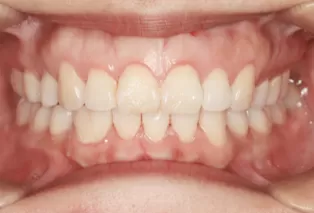

After Treatment

Intraoral photos after treatment